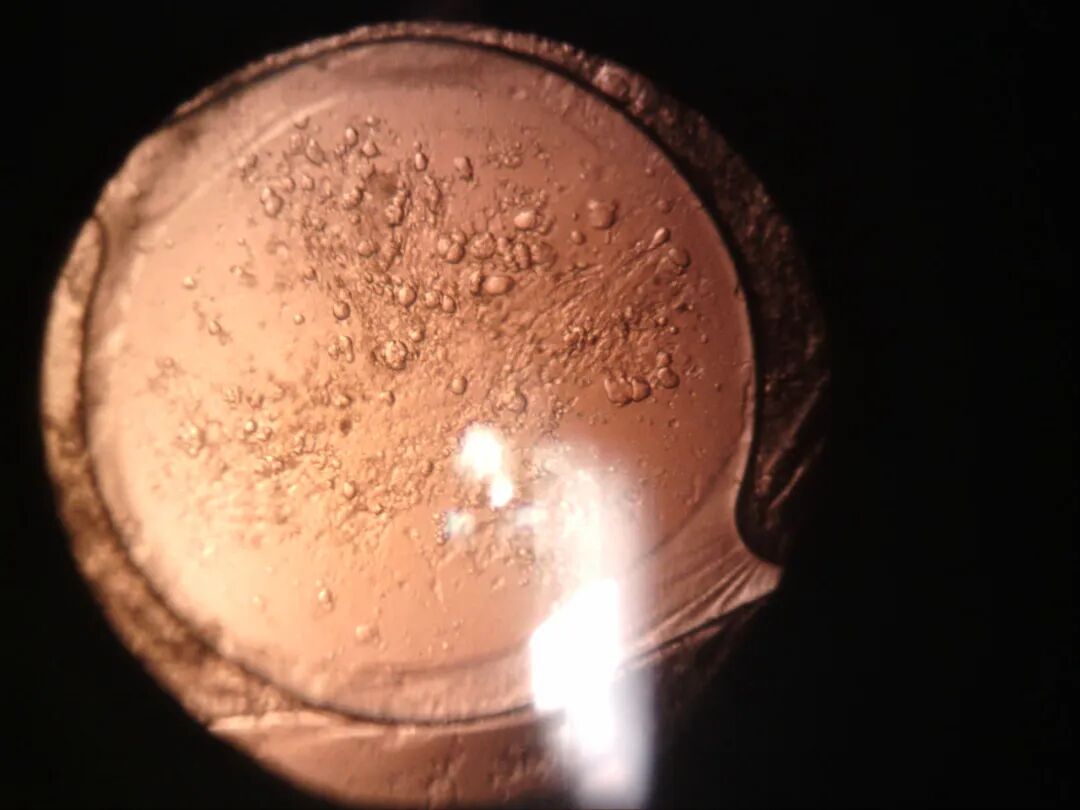

7.2 眼底反射

利用眼底反射光线,观察晶状体。

裂隙灯上光源是什么裂隙灯显微镜常用检查方法_https://www.jmylbn.com_新闻资讯_第14张

后发障

操作要点

• 需要散瞳

• 光源亮度:中等至最强亮光

• 裂隙宽度:3-4mm细窄至微宽

• 裂隙高度:<瞳孔

• 裂隙夹角:0°~15°,可调

• 放大倍率:16x或25x

• 裂隙光照射在瞳孔或虹膜与瞳孔边界,使眼底反射光聚焦在晶状体后囊

• 观察:晶状体、人工晶状体、悬韧带